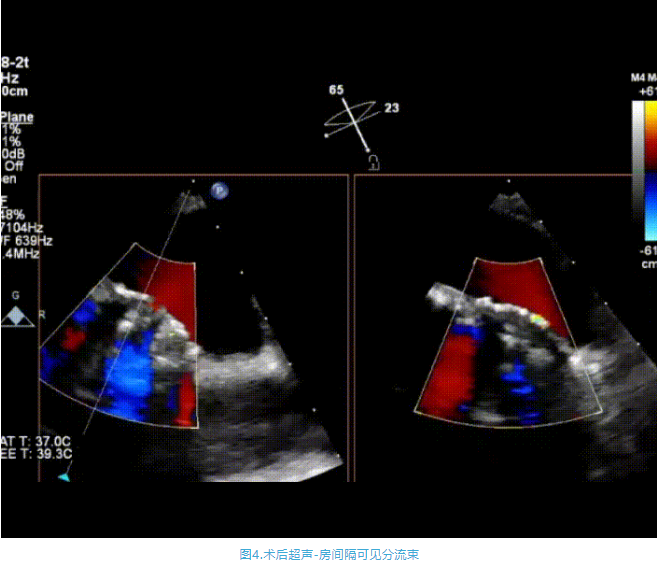

術(shù)中首先在局麻下穿刺股動(dòng)脈、股靜脈,完成心導(dǎo)管檢查評估后轉(zhuǎn)為全麻,在食道超聲引導(dǎo)下穿刺房間隔,穿刺成功后將加硬導(dǎo)絲送入左上肺靜脈建立軌道,根據(jù)患者病情行球囊預(yù)擴(kuò)張后植入6mm孔徑房間隔造孔支架,經(jīng)透視及食道超聲評估支架左右盤展開良好,夾持于房間隔兩側(cè),固定穩(wěn)定、位置良好,食道彩超顯示房水平右向左為主分流,分流孔直徑符合預(yù)期大小,心導(dǎo)管檢查評估達(dá)到預(yù)期效果,釋放造孔支架。術(shù)后12h患者下床活動(dòng),恢復(fù)順利,擬于近日完善術(shù)后評估后出院。

心房分流術(shù)是通過器械制造穩(wěn)定可控的心房間分流,適應(yīng)證包括藥物治療效果不佳的左心衰或肺動(dòng)脈高壓右心衰。本例患者為肺動(dòng)脈高壓右心衰,術(shù)中成功放置MicroFlux®造孔支架在房間隔理想位置上,創(chuàng)造穩(wěn)定可控的心房間分流(此例患者以右向左分流為主),在不顯著增加左心負(fù)擔(dān)的情況下,有效降低患者右心房壓力、緩解體循環(huán)淤血,增加左心輸出量,改善患者癥狀、活動(dòng)耐力和生存質(zhì)量。同時(shí),國內(nèi)外也已經(jīng)開展多項(xiàng)房間隔造孔支架在射血分?jǐn)?shù)保留、射血分?jǐn)?shù)中間值和射血分?jǐn)?shù)降低的左心衰患者中的臨床研究,結(jié)果顯示對于經(jīng)過充分的規(guī)范化藥物治療后仍控制不佳的患者,心房分流術(shù)可改善患者的癥狀及生存質(zhì)量?!   ?/p>